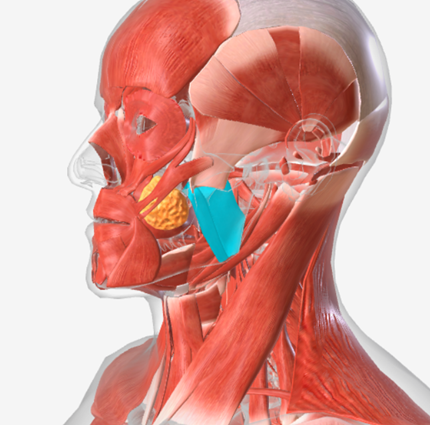

Masseter

origin is the zygomatic arch, coursing down to insert into the ramus of the mandible and the coronoid process, function is the elevate the mandible

Temporalis

origin is the temporal and parietal bones of the cranium, coursing down and forward through the zygomatic arch, to insert on the coronoid process and the ramus of the mandible; function is to elevate the mandible and draw it back if protruded

Medial pterygoid

origin is the medial pterygoid plate of the sphenoid bone, coursing down and back to the mandibular ramus; function is to elevate the mandible

Lateral pterygoid

origin is the lateral pterygoid plate and the greater wing of the sphenoid, coursing back to the mandible; function is to protrude the mandible

Masseter

|  |  |

Temporalis

|  |  |

Medial Pterygoid

|  |  |

Lateral Pterygoid

|  |  |